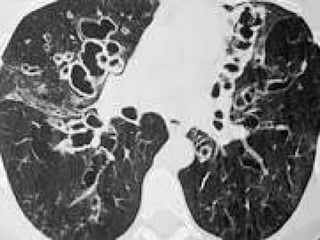

---BRONQUIECTASIAS– TOSSE COM SECREÇÕES

PURULENTAS E ABUNDANTES

CAVITAÇÃO PULMONAR

CAVITAÇÃO PULMONAR-- VÔMICA